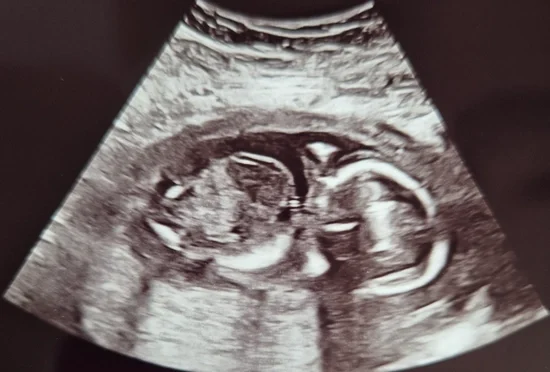

Beeld: Mandy

“De 20-weken echo”

Toen de echokop op mijn buik gezet werd, en het beeld verscheen zag ik het meteen. Dit ziet er niet goed uit, het beeld ziet er raar uit, dit klopt niet, nog voordat de echoscopiste iets vroeg/zei. Ze begon me vragen te stellen als; Wanneer had je voor het laatst controle, was alles toen goed, heb je nog wat gevoeld? Ze bleef nog even naar onze kleine kijken.

Er was geen hartslag meer bij onze kleine lieve schat. De echoscopiste heeft nog wat verder gekeken, en ze dacht, aan de grootte van de kleine te zien, dat het hartje mogelijk al rond de 17 weken was gestopt met kloppen.